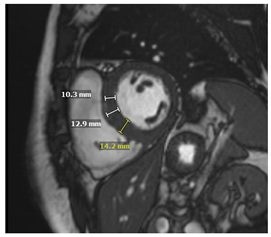

On CMR SSFP, better quantification of LV and papillary muscle mass can be made and tracked over time compared to echocardiography. Glycosphingolipid accumulation in myocytes results in a shorter T1 relaxation time on the T1 mapping sequence. In a systemic review, the mean T1 value in FD patients was 935 +/− 48 ms with a 1.5 T CMR scanner, compared to 999 + 31 ms in controls []. Shortened native T1 time has been described in individuals with FD without LVH and correlates with a reduced GLS on echocardiography []. Pseudo-normalization of native T1 time can be noted in areas of myocardial fibrosis or inflammation []. Native T2 mapping can show elevated T2 relaxation time in the basal inferolateral region or other areas of LGE, which reflects myocardial inflammation []. Post-contrast imaging would classically show a pattern of LGE involving the mid-myocardium of the basal inferolateral wall. However, LGE may become more extensive in advanced cases []. ECV values are normal in FD but may increase in areas of fibrosis. Key CMR findings in Fabry disease are summarized in Table 2.